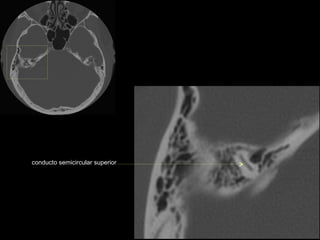

conducto semicircular

superior

conducto semicircular superior